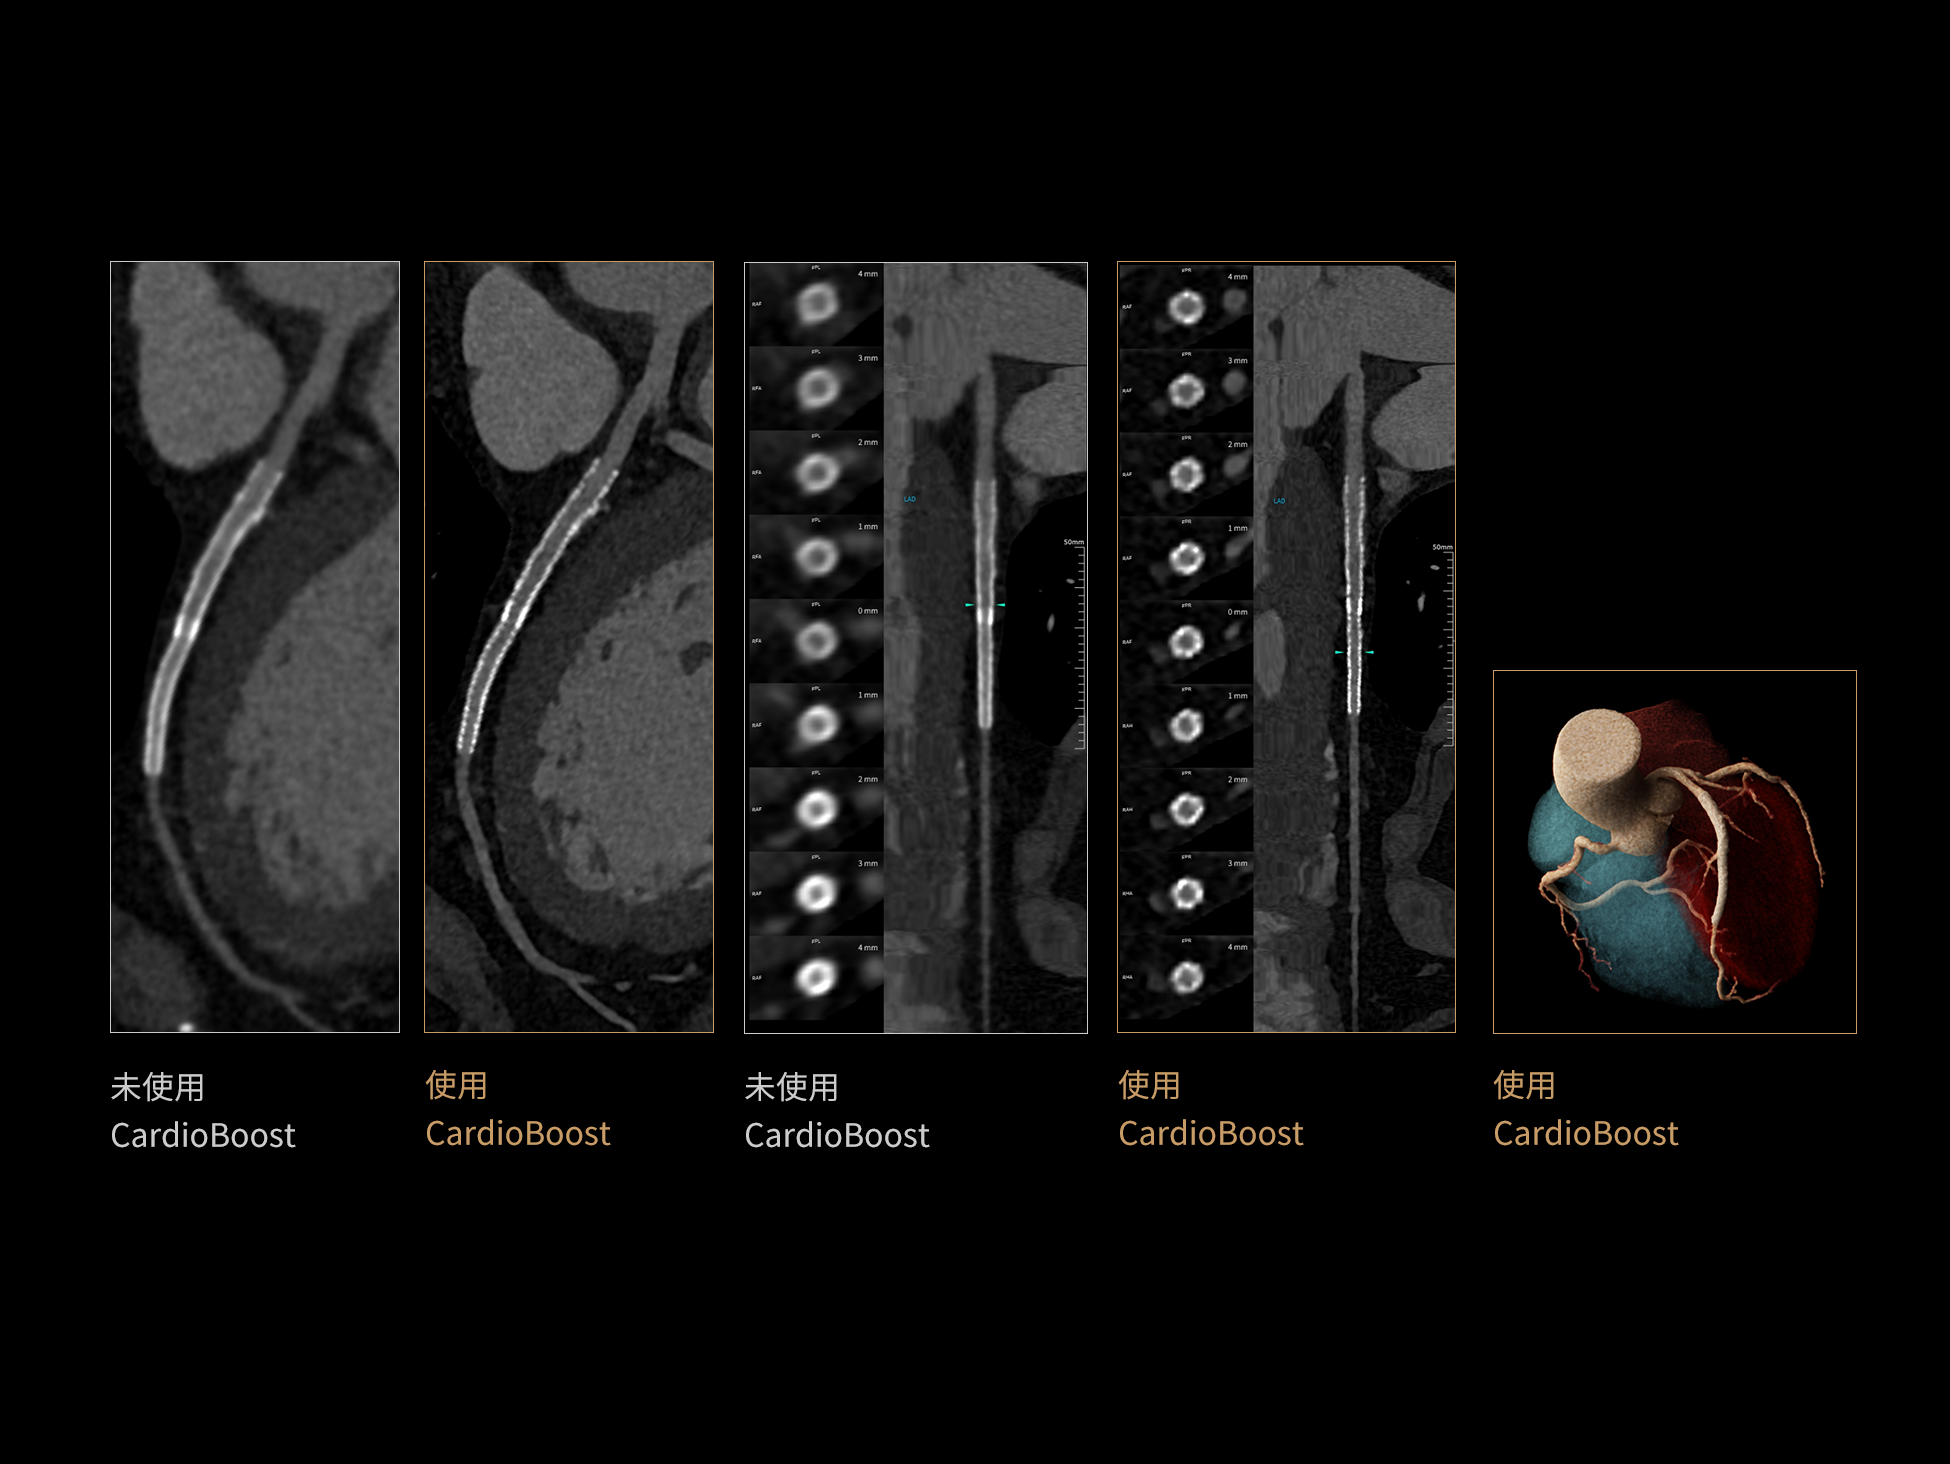

CardioBoost:专属网络设计,重塑心脏影像表现

uCT 868 搭载联影最新一代 uSense 人工智能平台,将智能化深度融入 CT 扫描全流程,从感知细微生理运动到精细结构探测,再到多场景诊疗优化。以 AI 为核心驱动力,uSense 重塑成像各环节,打造高效、高清的智慧扫查体验。在心脏成像领域,uSense 结合宽体探测器、心脏专研AI重建算法与AI冠脉运动追焦技术,在保持低剂量的同时,有效抑制运动伪影,精准呈现软斑块、混合型斑块及支架细节,助力冠脉成像惠及更多患者。针对多科室疾病临床应用场景,uSense 平台提供全方位的智能解决方案:包括头部运动伪影智能校正、金属植入物伪影抑制、扫描视野扩展等先进算法。这些创新技术使 uCT 868 能够构建覆盖全场景的智能诊疗体系,持续拓展 AI 赋能医学影像的边界。

作为高端CT解决方案平台,uCT 868 凭借高速扫描能力、宽体探测器、AI驱动重建算法和智能工作流,能够从容应对上述急症场景下的多部位、多模式联合检查需求。不论是冠脉、主动脉与肺动脉的一站式成像,还是卒中的快速识别,亦或是全身创伤评估中的快速定位与精细结构显示,uCT 868 均能以高速、清晰、低剂量的成像表现,助力临床在关键时刻做出快速而准确的诊断判断,赢得宝贵救治时间。